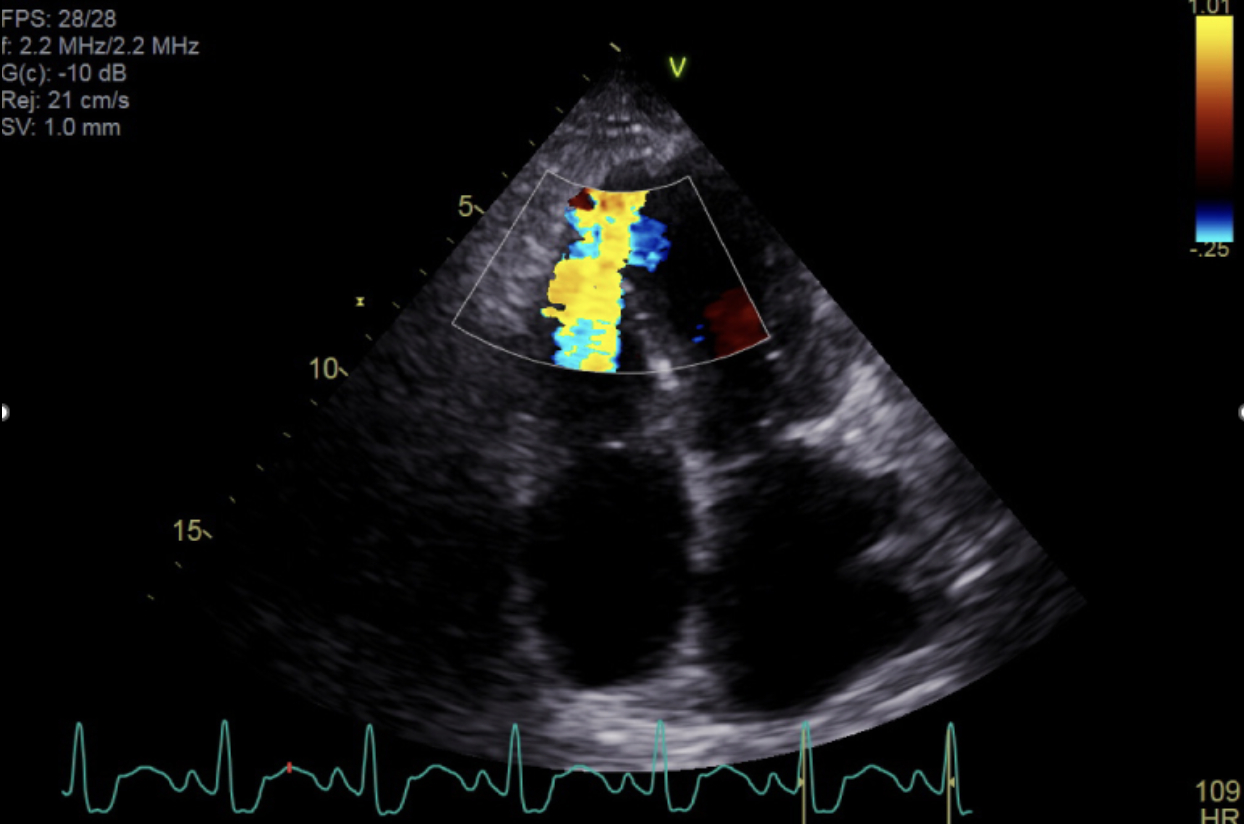

Her course was complicated by new-onset atrial fibrillation with RVR. Despite IV amiodarone, RVR persisted, along with worsening respiratory status and increasing vasopressors needs. Limited echocardiography revealed basal hypercontractility and dynamic LV outflow tract obstruction (LVOTO). Esmolol was considered to reduce the gradient. Simultaneously, pulmonary artery catheter readings suggested new left-to-right shunting. A new loud holosystolic murmur was heard, and repeat echocardiogram confirmed a large ventricular septal rupture (VSR).